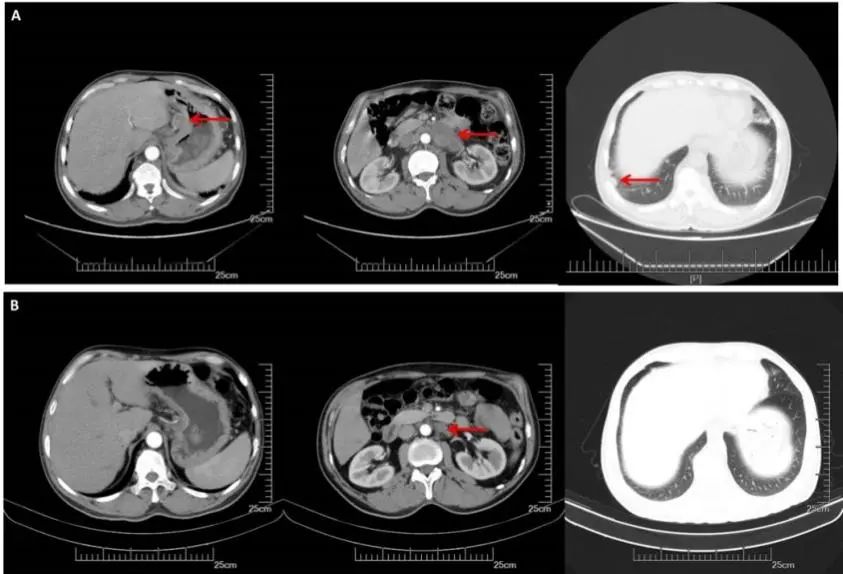

CT(2017.9.29):1、胃癌术后改变,吻合口增厚,较前减轻。腹膜后可见多发增大淋巴结影。右侧锁骨上、双侧膈肌脚后及纵隔内见多发淋巴结,部分较前增大,双肺散在小结节,较前变化不大。

CT(2018.3.27):胃癌术后改变,吻合口增厚,较前减轻。腹膜后可见多发增大淋巴结影,较前缩小。右侧锁骨上、双侧膈肌脚后及纵隔内见多发淋巴结,部分较前增大。双肺散在小结节,较前变化不大。

A:CT增强(2017.09.29):右锁骨上,纵膈,腹腔淋巴结明显增大,双肺无明显变化;B:CT增强(2018.03.27):腹膜后多发增大淋巴结较前缩小,右侧锁骨上纵隔内见多发淋巴结,部分较前增大,双肺较前变化不大。